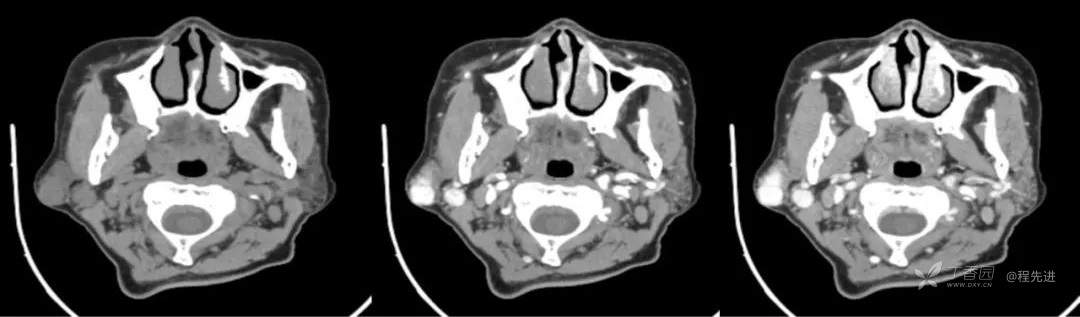

简要病史:发现右侧耳下肿物12年,不痛,缓慢生长

既往史:19年前因右侧腮腺肿物在当地医院行手术(具体不详),17年前因右侧腮腺肿物复发再次在当地医院手术(具体不详)

体格检查:右侧耳下可扪及大小约3*3cm肿物,质地中,边界清,活动可,无明显压痛。颈部未扪及明显肿大淋巴结